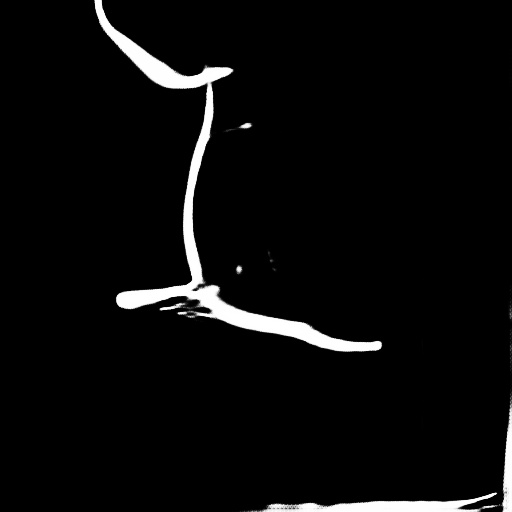

| (a) Vessel mask | (b) Distance transform | (c) Vessel motion |

As for the foreground, we observe that the contrast agent flows out from the catheter. Therefore, we consider the Eulerian motion field, as shown in Figure 4, to be a more reasonable specification of blood flow behavior compared to the traditional motion field.

Parallel loss.

Clearly, the direction of blood flow should align with the course of blood vessels (Figure 4). Hence, we design the parallel loss to achieve a parallel alignment between them. Initially, we conduct skeletonization and distance transform on the masks obtained from Section 3.1, and calculate pixel-wise cosine similarity between these transformed masks and the predicted flow: